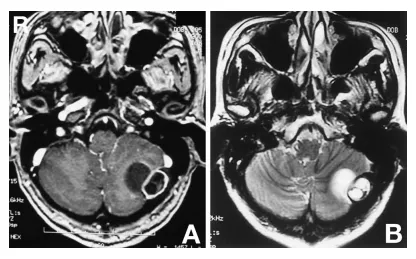

钆增强T1加权磁共振成像显示,板障内部分呈低信号伴环形强化,小脑内部分呈低信号(图3A)。T2加权磁共振成像显示硬膜外部分呈高信号,硬膜下部分呈高信号并延伸至小脑(图3B)。

图3A:钆增强T1加权磁共振成像显示一哑铃型肿瘤,由一伴有边缘环形强化的硬膜外部分和一有包膜的硬膜下部分构成。B:T2加权磁共振成像显示板障内部分信号强度不均,小脑内部分呈高信号。